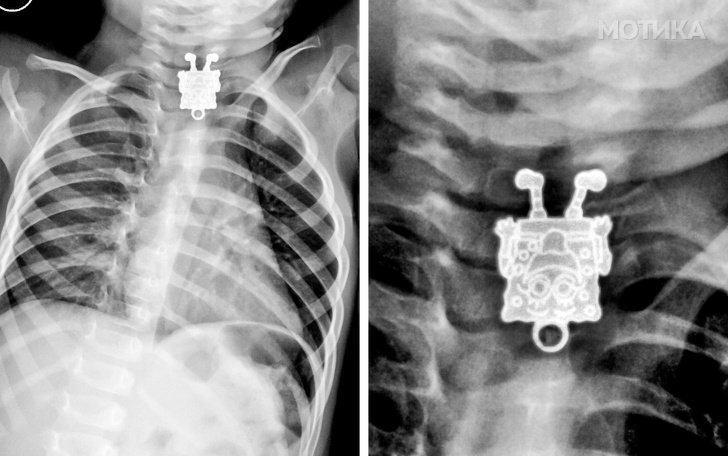

3. Детето проголтало приврзок во форма на Сунѓерот Боб